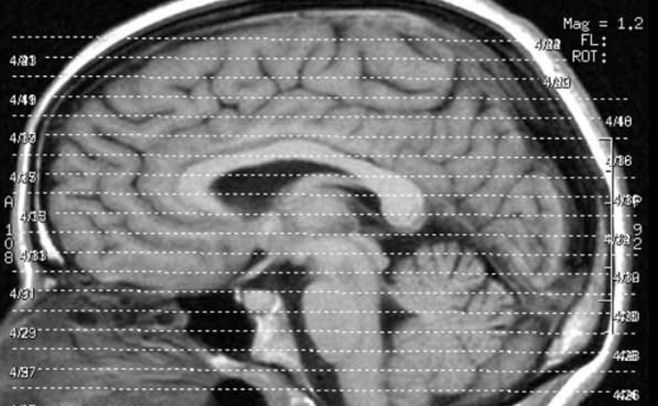

Cerebro

Flickr.com/Liz_Henry

Las experiencias cercanas a la muerte son fruto de una anomalía cerebral, según dijo en una entrevista con Efe el catedrático de Neurobiología de la Universidad de Amsterdam, Dick Swaab.